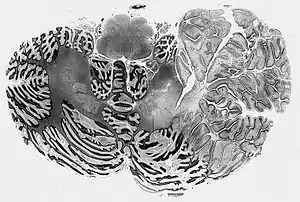

| Dysplastic cerebellar gangliocytoma histology | |

MICROSCOPY (lhermitte-duclos disease) 1>Enlarged circumscribed cerebellar folia 2>internal granular layer is focally indistinct and is occupied by large ganglion cells 3>myelinated tracks in outer molecular layer 4>underlying white matter is atrophic and gliotic

In Lhermitte–Duclos disease, the cerebellar cortex loses its normal architecture, and forms a hamartoma in the cerebellar hemispheres. The tumors are usually found on the left cerebellar hemisphere, and consist of abnormal hypertrophic ganglion cells that are somewhat similar to Purkinje cells. The amount of white matter in the cerebellum is diminished. Like cowden syndrome, patients with Lhermitte–Duclos disease often have mutations in enzymes involved in the Akt/PKB signaling pathway, which plays a role in cell growth. Mutation in PTEN gene on chromosome no. 10q leads to increased activity of AKT and mTOR pathways.